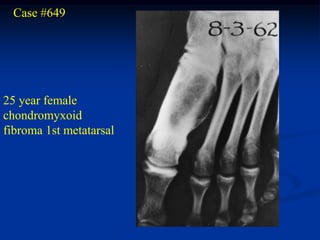

Case #649

25 year female

chondromyxoid

fibroma 1st metatarsal

Oblique view

Photomic